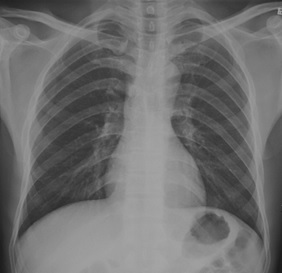

試題:根據(jù)下圖請做出正確診斷

A.正常胸片

B.肺門淋巴結(jié)腫大

C.肺炎

D.主動脈型心(靴型心)